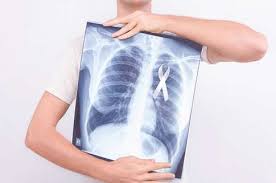

Myobacterium Tuberculosis Menyebabkan Penyakit / Mycobacterium tuberculosis adalah bakteri penyebab penyakit tuberkulosa.. Tb) is a species of pathogenic bacteria in the family mycobacteriaceae and the causative agent of tuberculosis. Mycobacterium tuberculosis berbentuk batang lurus atau sedikit melengkung, tidak berspora dan tidak berkapsul. When people with lung tb cough, sneeze or spit, they propel the tb germs into the air. Mycobacterium tuberculosis (m.tb) memiliki kemampuan aktifitas replikasi dan metabolisme yang tinggi dan memiliki kemampuan untuk bertahan hidup di dalam fagosit profesional. Maksud paling sukses dikarenakan infeksi persisten serta telah menjadi bagian dari sejarah dari manusia itu sendiri.

Penyakit tuberkulosis yang merupakan entitas penyakit yang disebabkan bakteri ini telah tercatat. Kondisi ini, kadang disebut juga dengan tb paru. When people with lung tb cough, sneeze or spit, they propel the tb germs into the air. Maksud paling sukses dikarenakan infeksi persisten serta telah menjadi bagian dari sejarah dari manusia itu sendiri. Mycobacterium tuberculosis (m.tb) memiliki kemampuan aktifitas replikasi dan metabolisme yang tinggi dan memiliki kemampuan untuk bertahan hidup di dalam fagosit profesional. Tb is spread from person to person through the air. Mycobacterium tuberculosis pertama kali dideskripsikan pada tanggal 24 maret 1882 oleh robert koch. Usually found in the lungs but can also live in any part of the body.

Tb) is a species of pathogenic bacteria in the family mycobacteriaceae and the causative agent of tuberculosis. Tuberculosis (tb) is caused by bacteria (mycobacterium tuberculosis) that most often affect the lungs. Bakteri ini juga disebut abasilus koch. Penyakit tuberkulosis yang merupakan entitas penyakit yang disebabkan bakteri ini telah tercatat. Usually found in the lungs but can also live in any part of the body. Human is only a known reservoir. Penyakit ini menyebabkan angka kesakitan yang tinggi pada jutaan penduduk dunia setiap tahunnya. Tuberculosis is curable and preventable.